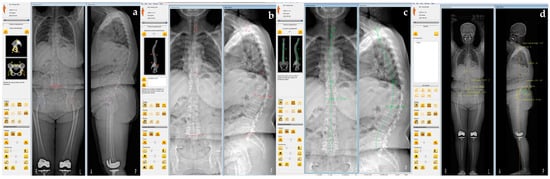

3.6. Representative Case